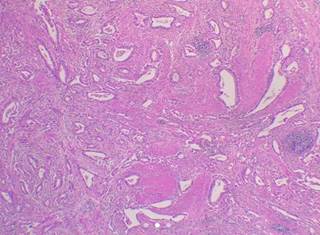

Mujer de 61 años, con antecedente de gastrectomía distal por tumor exofítico en el antro y píloro con reporte histopatológico (Figura 1), adenocarcinoma gástrico invasor, con gastroyeyunostomía en Y de Roux, quimioterapia y radiación casi tres años antes de su presentación aguda. Inicia con malestar general, pérdida de peso y anemia grado III (OMS). Con tomografía computarizada que mostró engrosamiento de la pared rectal con involucro a útero. La colonoscopia reporta zona de induración a 5 cm del margen anal, por lo que se realiza resección del segmento de recto e histerectomía total (Figura 2) con reporte de adenocarcinoma moderadamente diferenciado compatible morfológicamente con primario gástrico (Figura 3), la paciente tuvo adecuada recuperación clínica, con tratamiento quimoterapéutico adyuvante.

Figura 1: Adenocarcinoma gástrico invasor, moderadamente diferenciado (grado histológico 2) o clasificación de Lauren (adenocarcinoma de tipo intestinal) o bien clasificación OMS 2019 (subtipo tubular). Localización del tumor: pared anterior y posterior del antro y píloro.